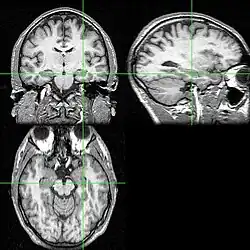

Associated neural activity

Recent research using neuro-imaging technology including PET and fMRI scanning has shown that there is an extensive amount of distributed brain activation during the process of episodic encoding and retrieval. Among the various regions, the two most active areas during the constructive processes are the medial temporal lobe (including the hippocampus) and the prefrontal cortex.[15] The Medial Temporal lobe is especially vital for encoding novel events in episodic networks, with the Hippocampus acting as one of the central locations that acts to both combine and later separate the various features of an event.[16][17] Most popular research holds that the Hippocampus becomes less important in long term memory functioning after more extensive consolidation of the distinct features present at the time of episode encoding has occurred. In this way long term episodic functioning moves away from the CA3 region of the Hippocampal formation into the neocortex, effectively freeing up the CA3 area for more initial processing.[17] Studies have also consistently linked the activity of the Prefrontal Cortex, especially that which occurs in the right hemisphere, to the process of retrieval.[18] The Prefrontal cortex appears to be utilized for executive functioning primarily for directing the focus of attention during retrieval processing, as well as for setting the appropriate criterion required to find the desired target memory.[15]